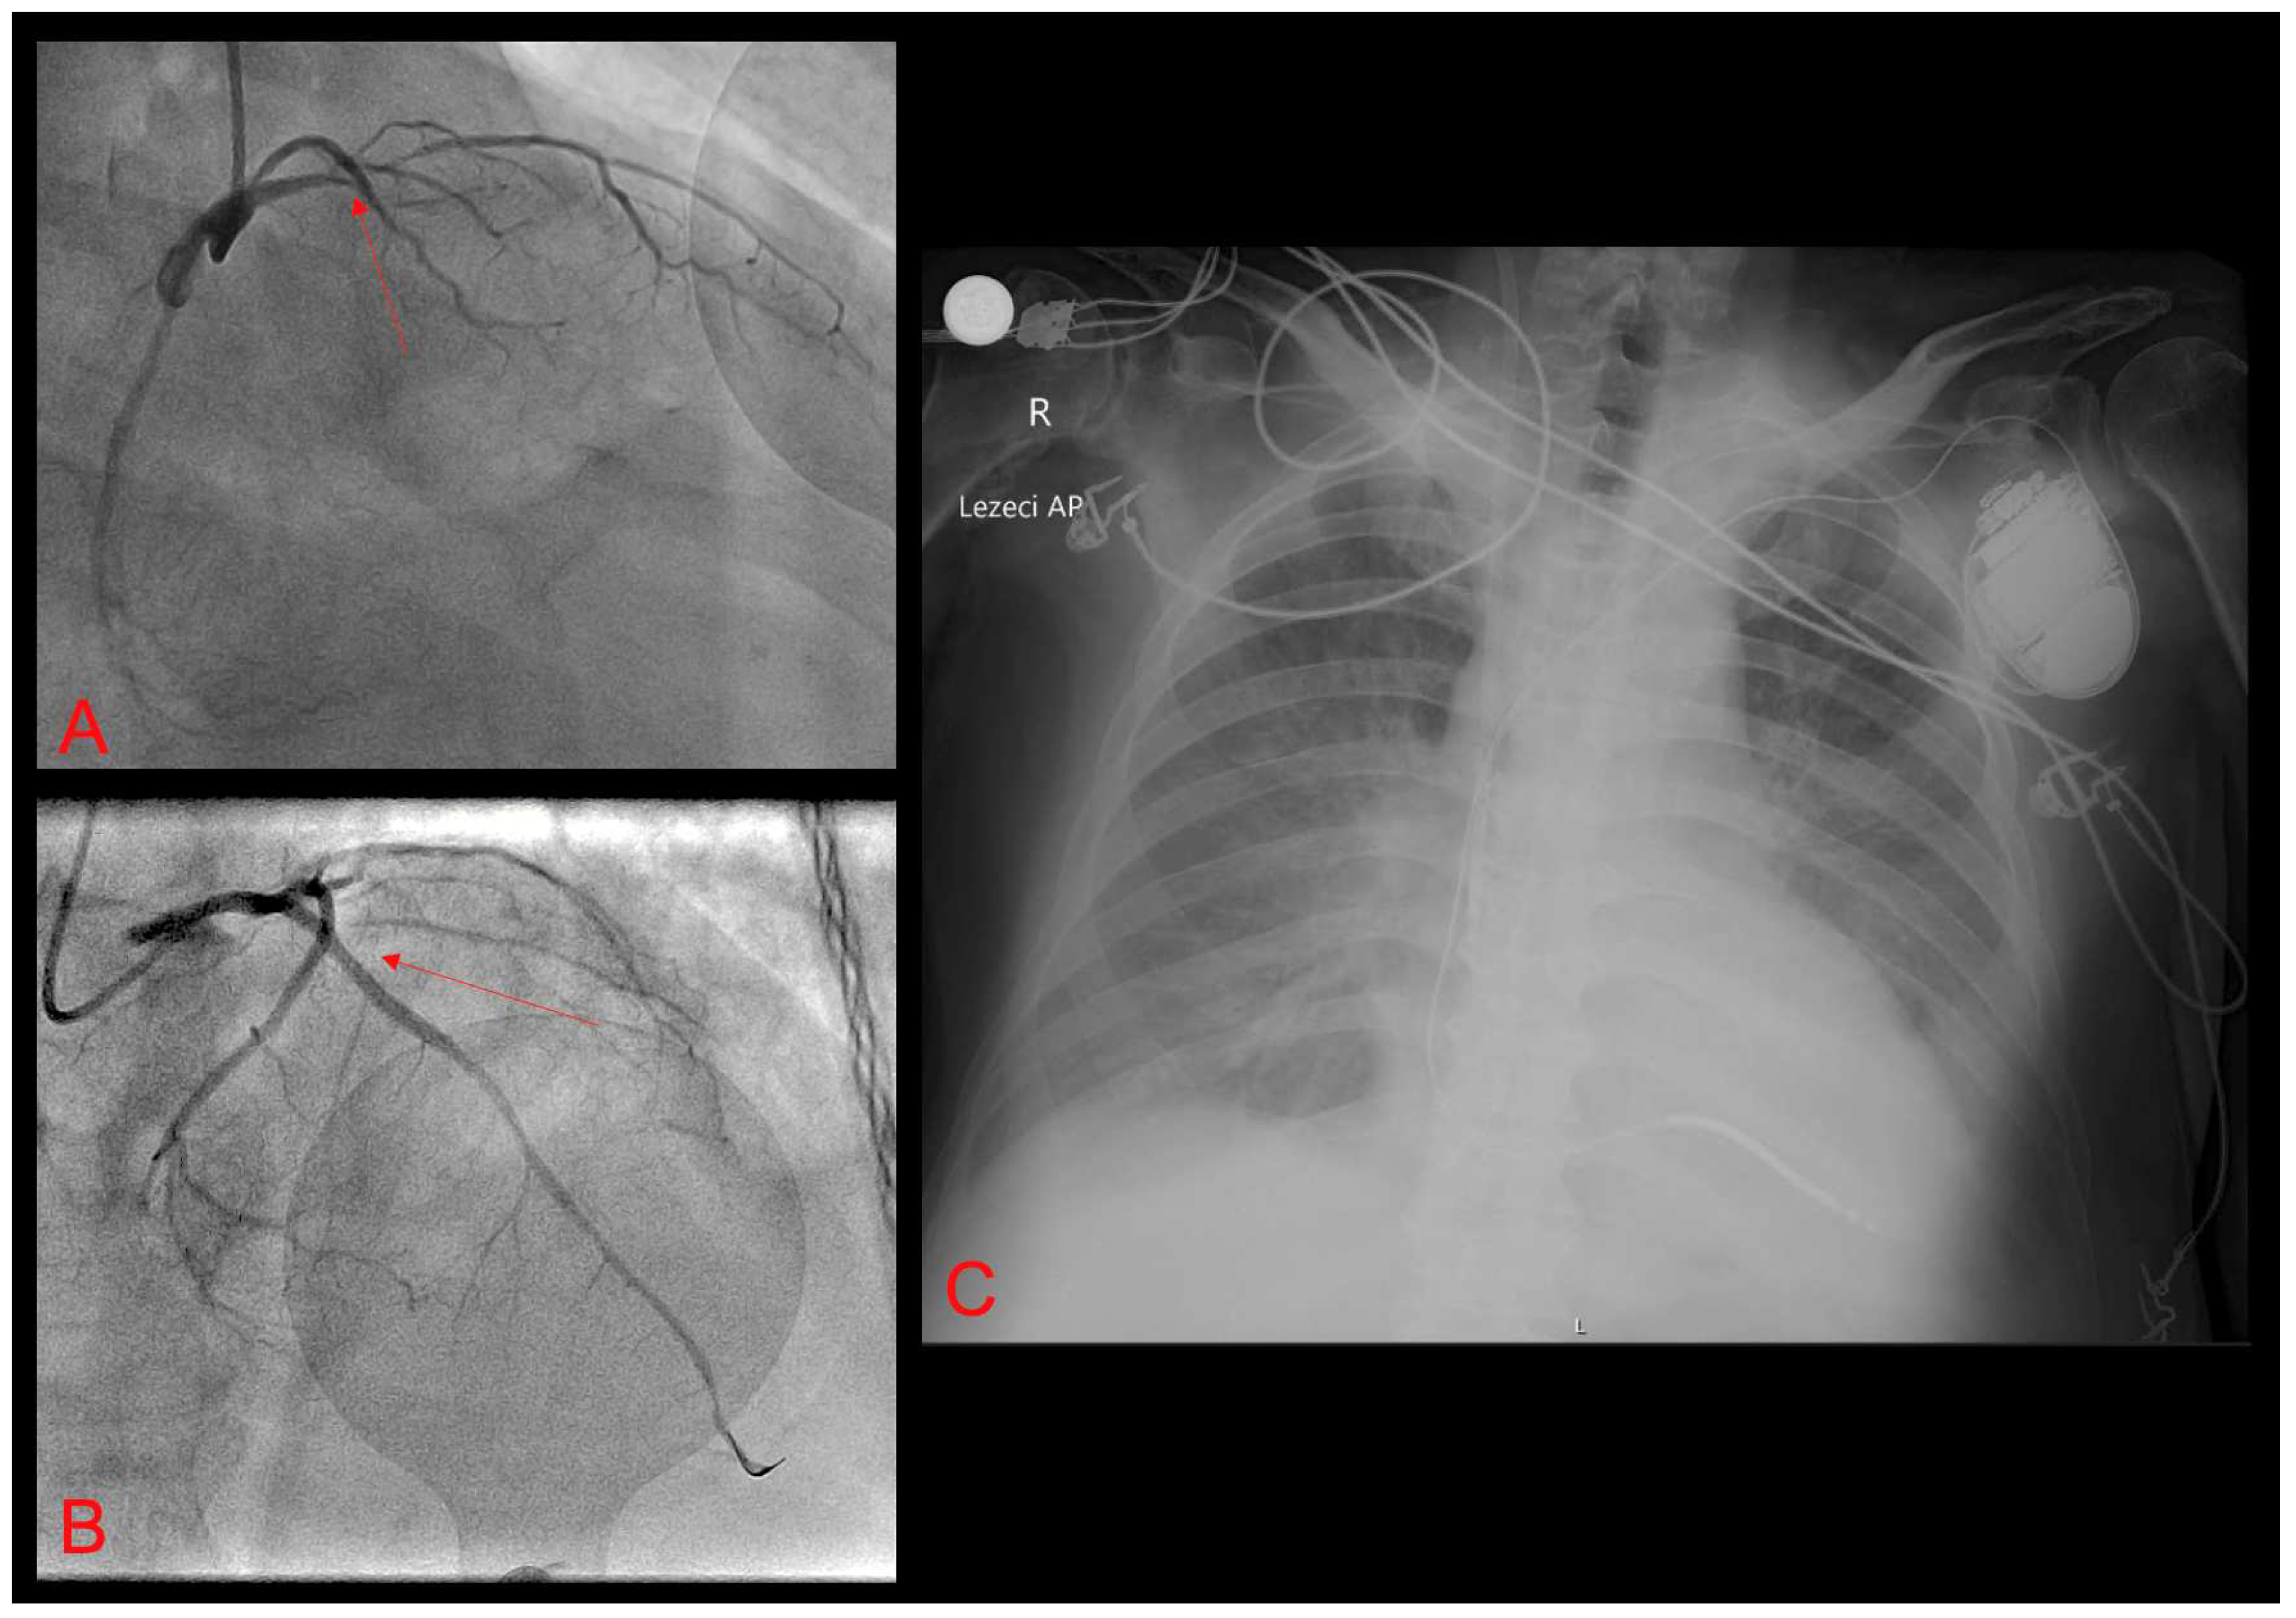

2. Case Report